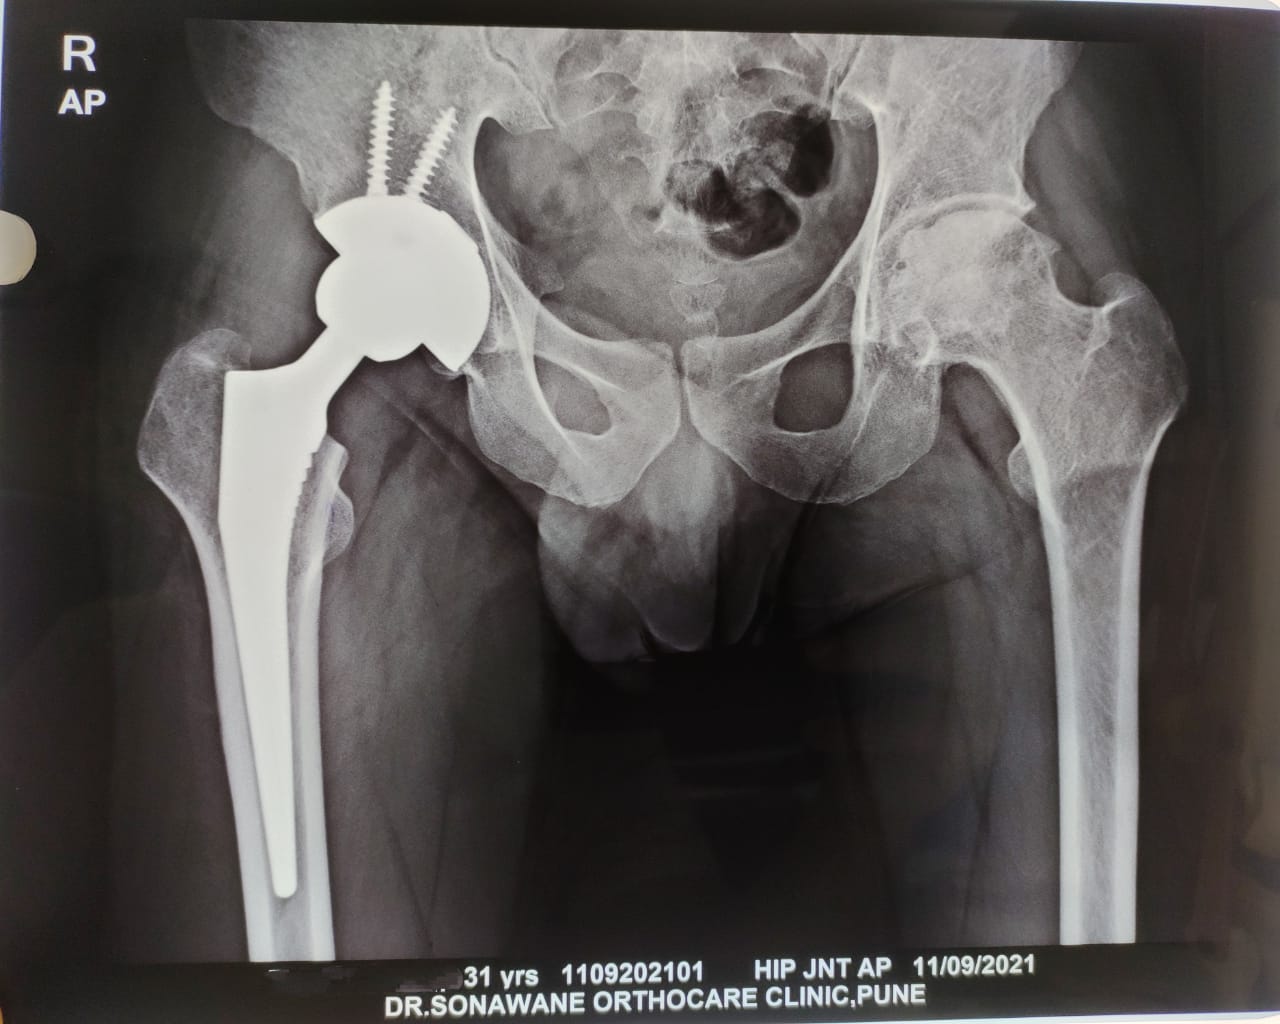

Dr. Sonawane Orthocare clinic is a centrally located Orthopedic Clinic In Pune city near Swargate at Hirabaug Business Centre, Hirabaug chowk, Tilak Road, Shukrawar peth and has easy accessibility from all parts of the city with multiple modes of travelling and enough parking spaces for patients’ own vehicles. Clinic is very modern and stylish and has air conditioned waiting area with comfortable sitting arrangement along with other amenities like TV, Wi-Fi, newspapers. There is hassle-free appointment and consultation system which is totally computerized. Patients get system generated appointment messages, reminders for follow-up dates and prescriptions through messages and emails. So its easy to keep track, keep and carry records and access it anywhere in the world. Clinic offers in-house digital X-ray, pathology tests and physiotherapy facilities at very reasonable rates. This makes the clinic a one stop destination for the patients they don’t need to go anywhere else for these facilities, saving lots of time and effort to get the treatment. We at Dr. Sonawane Orthocare clinic are committed for the best orthopedics care and proud to be one of the best orthopedics clinics in Pune.